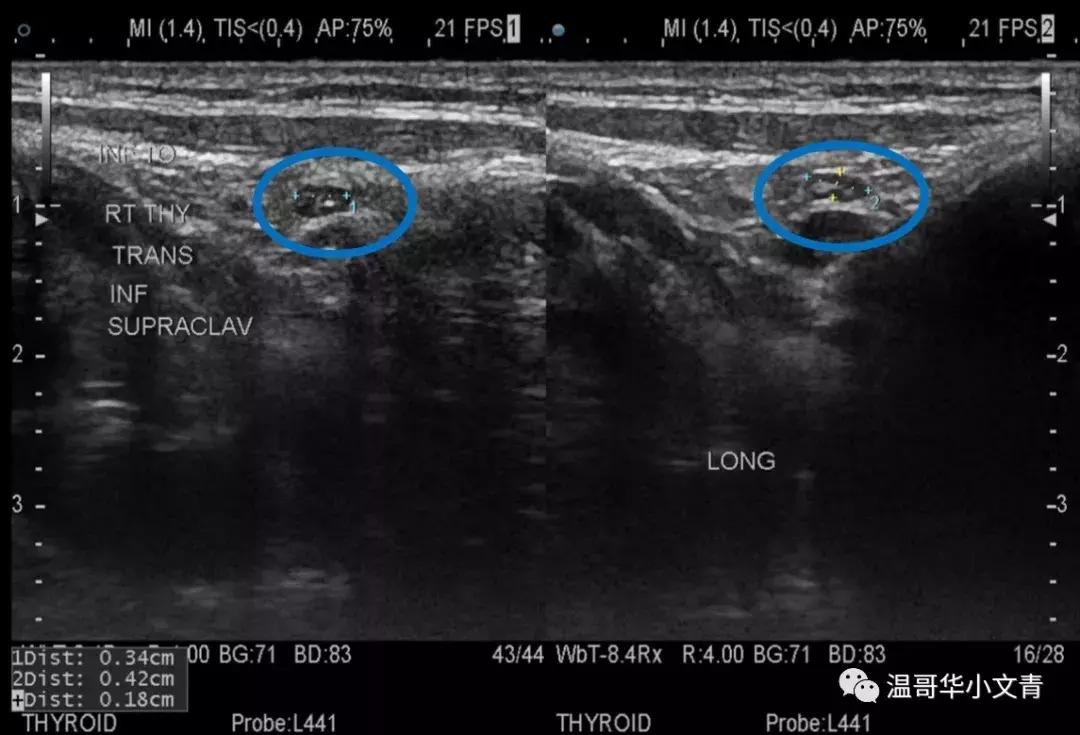

第三个图是一个术前发现的气管旁甲状腺下方可疑淋巴结,淋巴结长径是4毫米。在这个淋巴结中间你能看到明显的钙化,基本证明了这是一个转移淋巴结,术后病理显示这个淋巴结里的转移灶是2毫米。

第四个图是一个术前发现的气管旁甲状腺后方可疑淋巴结,淋巴结长径是4毫米。这个淋巴结也是比较圆,边界不规则,比较可疑,术后病理显示这个淋巴结里的转移灶是3毫米。